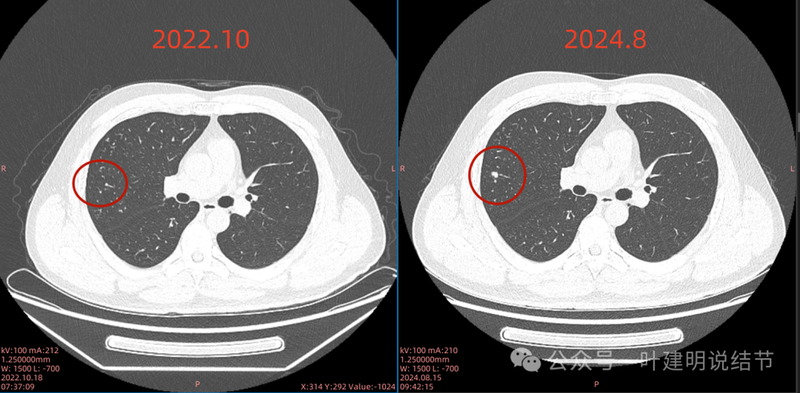

与既往对比影像:

2022年10月主病灶处没有异常。

2022年时右中叶处本来就有的。